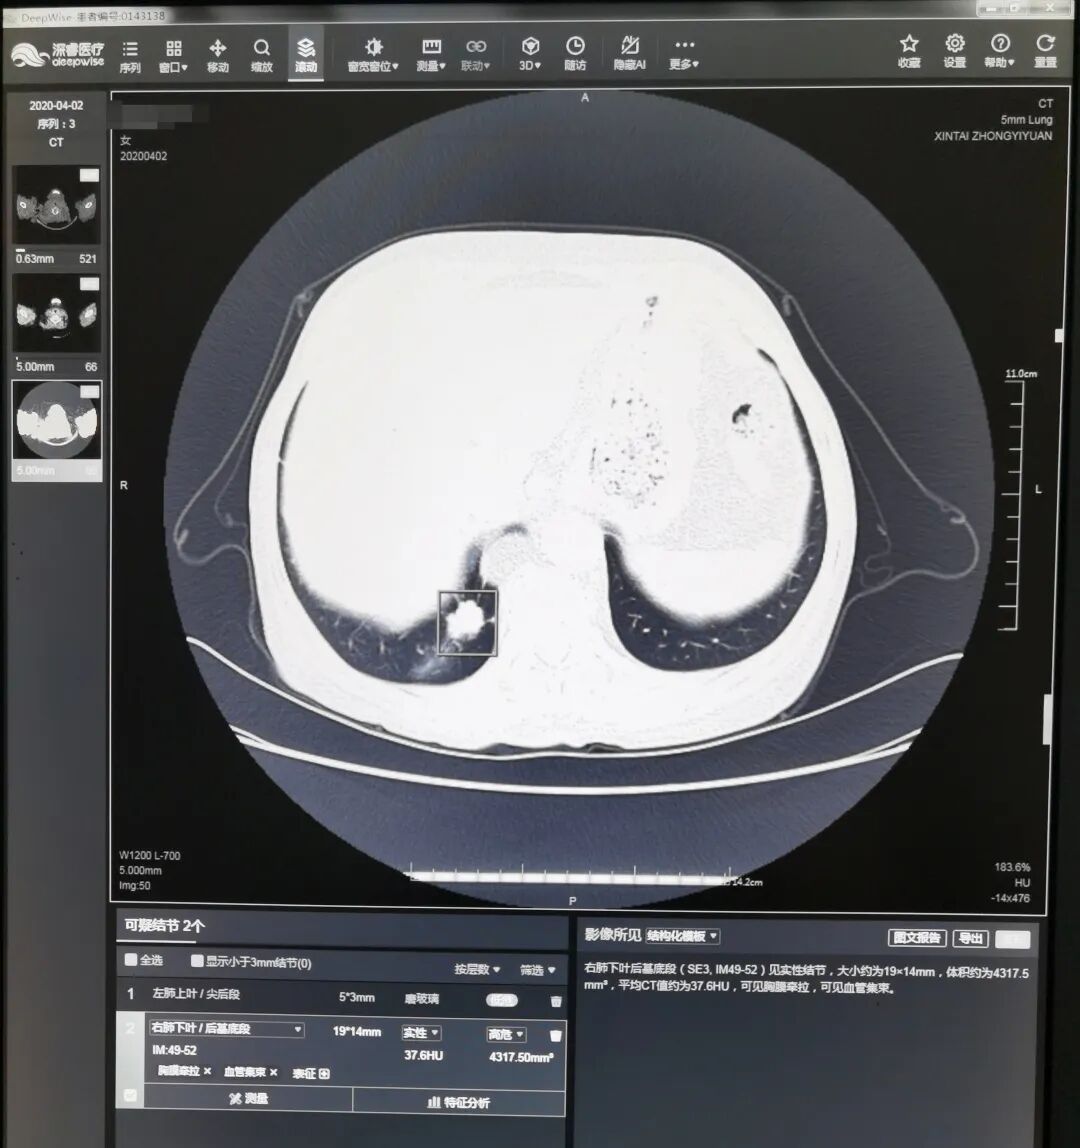

“人工智能(AI)系统可以对每一副图像进行地毯式筛查,避免因为经验差异和医生的视疲劳造成的漏诊。”李美介绍,传统人工筛查需要医生逐个区域用鼠标不停地拖曳、放大,用肉眼一点点甄别影像的每一处可疑部位,一般需要用时3—5分钟,有的疑难的影像片甚至需要更长时间。而人工智能肺小结节筛查系统,基于数十万份高质量胸部CT数据的神经网络深度学习、多维训练,相当于把数十万份由专家诊断的肺小结节大数据植入系统,作为强大支撑作出判断。借助人工智能的力量,系统即能快速对所有完成的胸部低剂量螺旋CT扫描图像进行筛查,并自动对可疑肺小结节进行精准定位,用色框清晰标注小结节坐标提示医生,并对结节的可疑病灶数、性质、直径、体积、CT值等信息以及影像学表现进行描述,医生就可以对这些有问题的地方着重处理。

如图显示,AI软件可以自动识别3mm以上的实性结节、磨玻璃结节(绿方框所示),省去医生寻找的时间